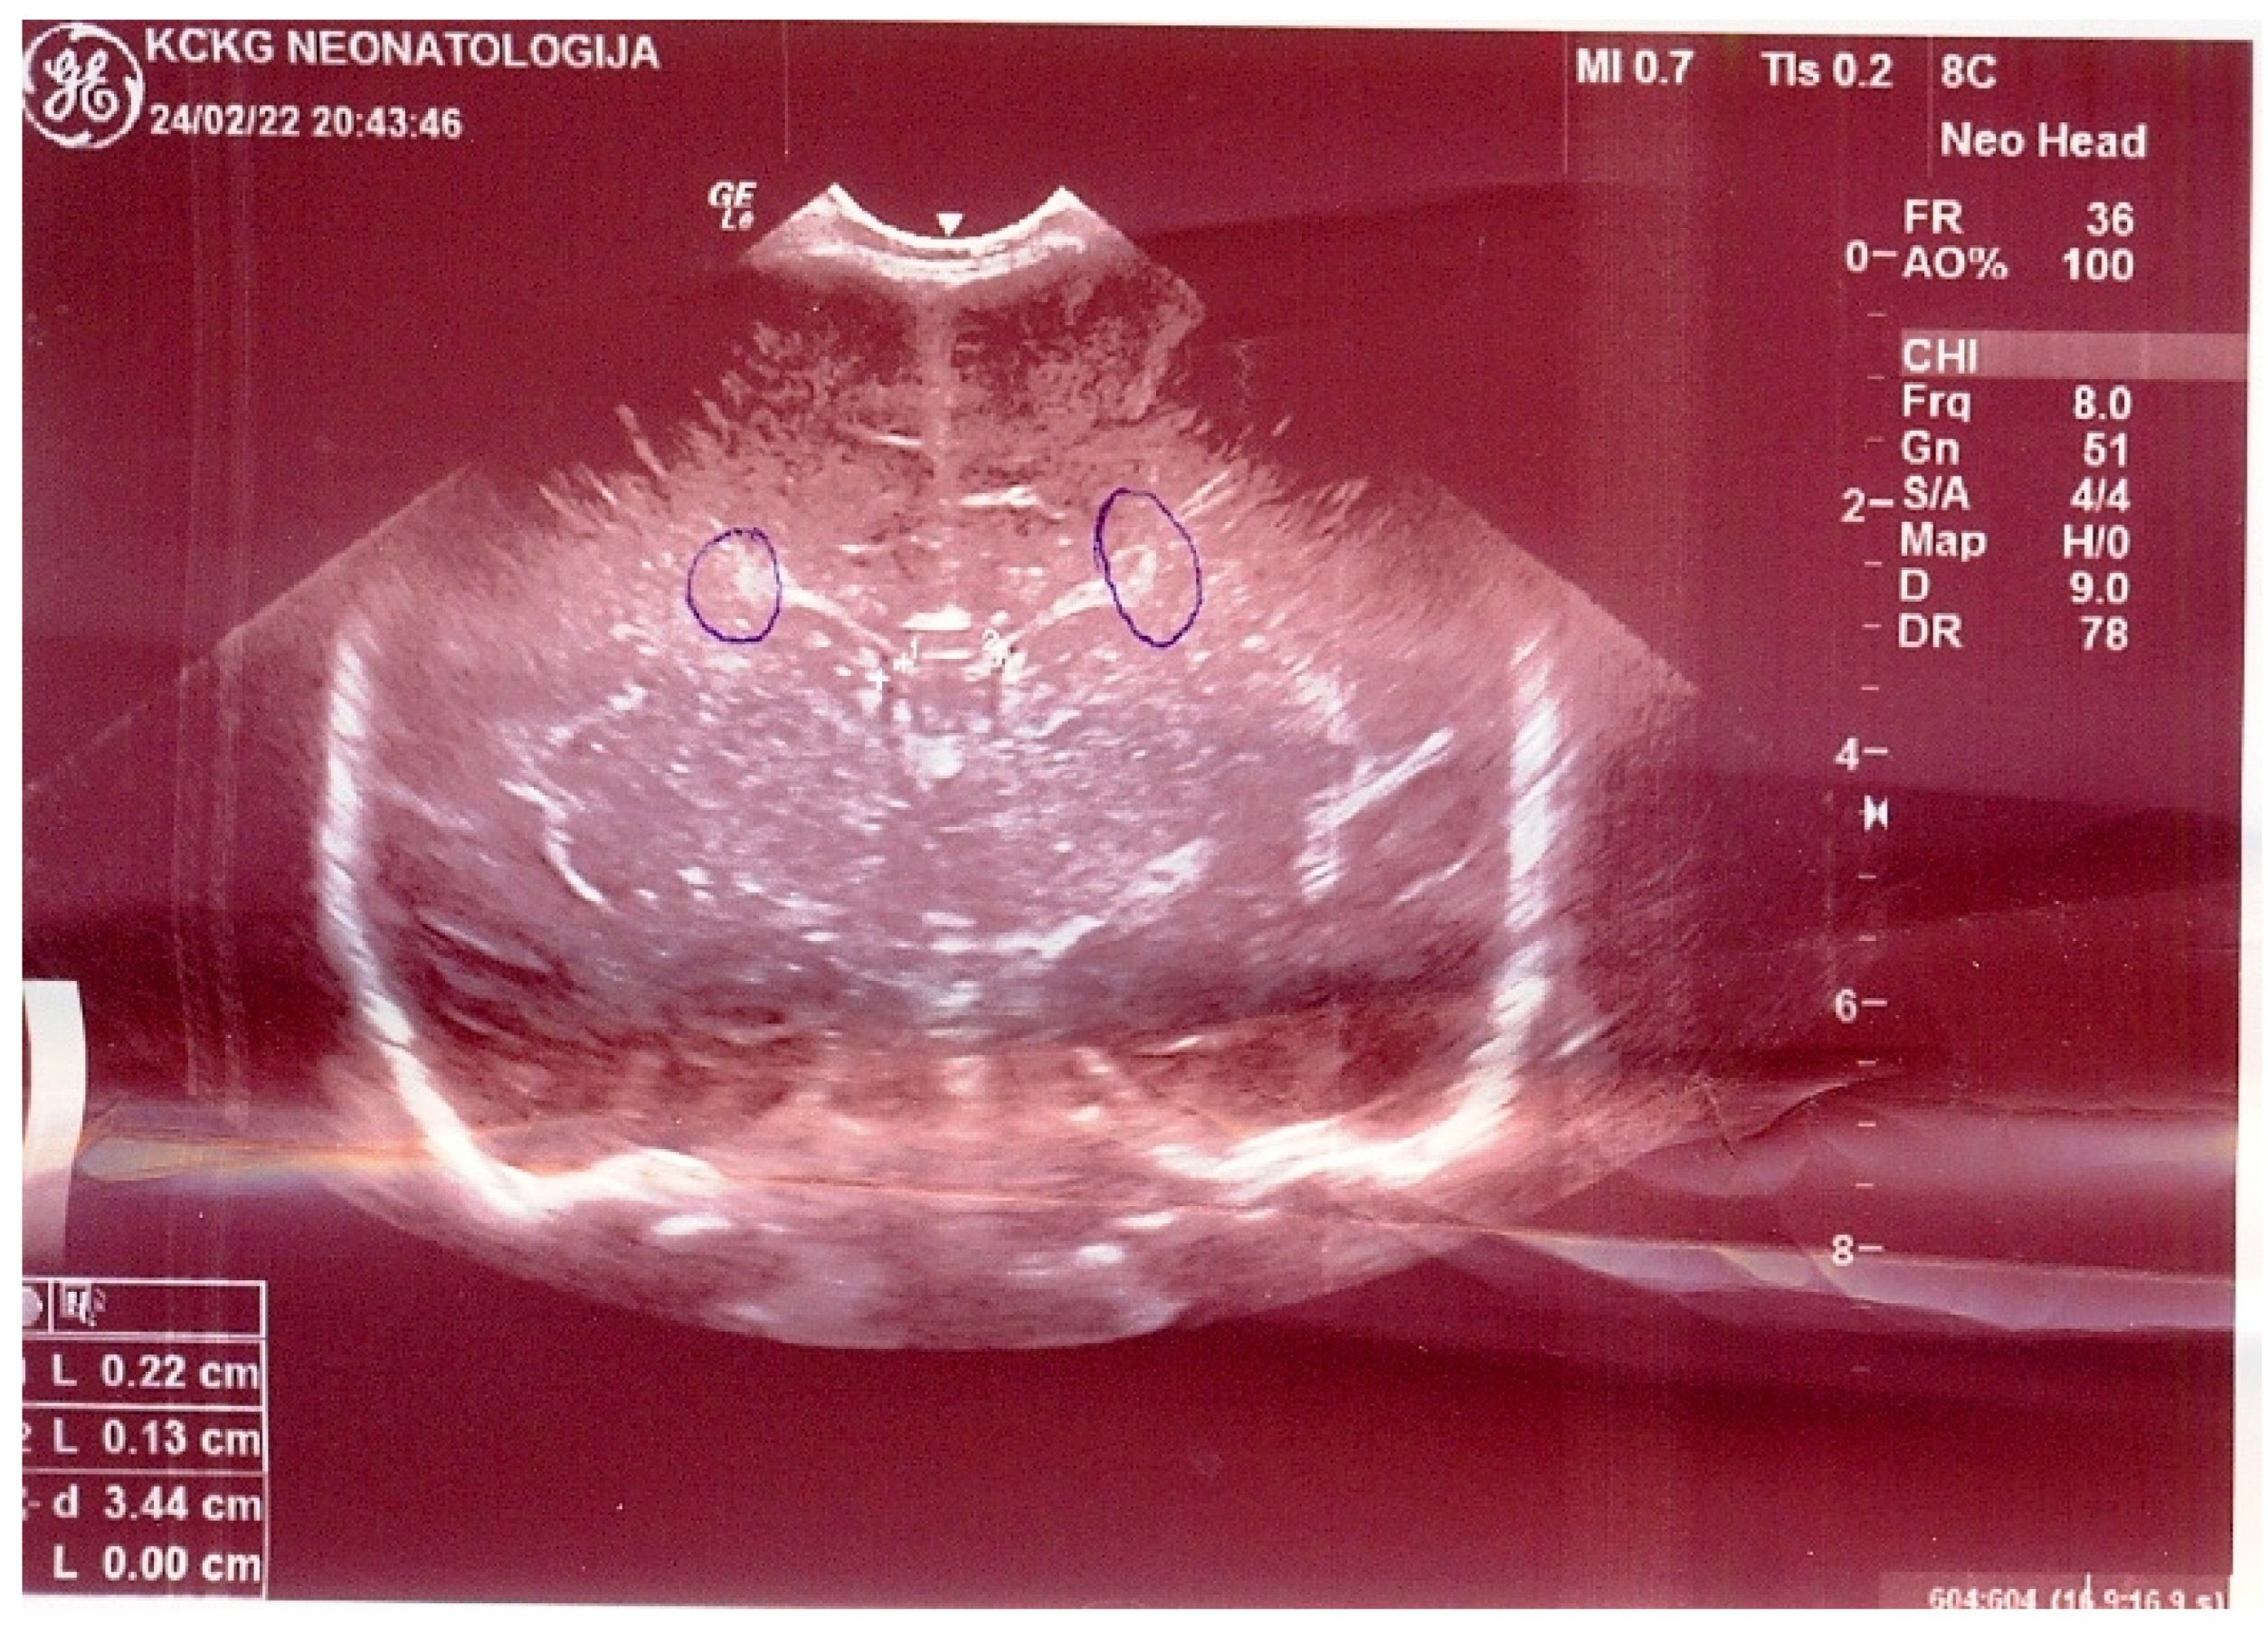

2. Commentary